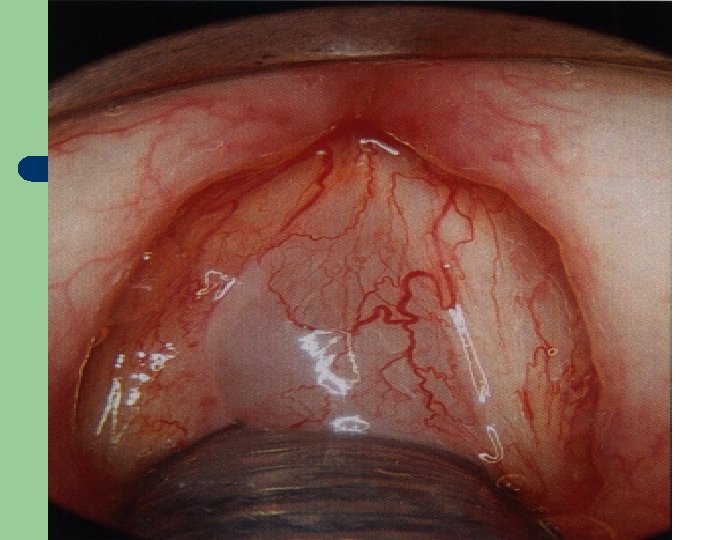

Vývoj dětské chraptivosti l 1. 2. 3. 4. Průvodním jevem při dětské chraptivosti je pokašlávání a pochrchlávání. Nález na hlasivkách postupuje takto: Hyperemické (překrvené hlasivky, Hypertrofické, vřetenovité zduření, hlasivkový uzávěr je neúplný a hlas má dyšnou příměs, ventrikulární řasy se začínají vyklenovat Zpěvácké uzlíčky, nejčastěji na hranicích přední a střední třetiny hlasivek Atrofie hlasivek až s podélnou rýhou, při fonaci nedomykavost uzávěru.

Hlasivkový uzlík l

Hlasivkový uzlík l

Hlasivkové uzlíky l